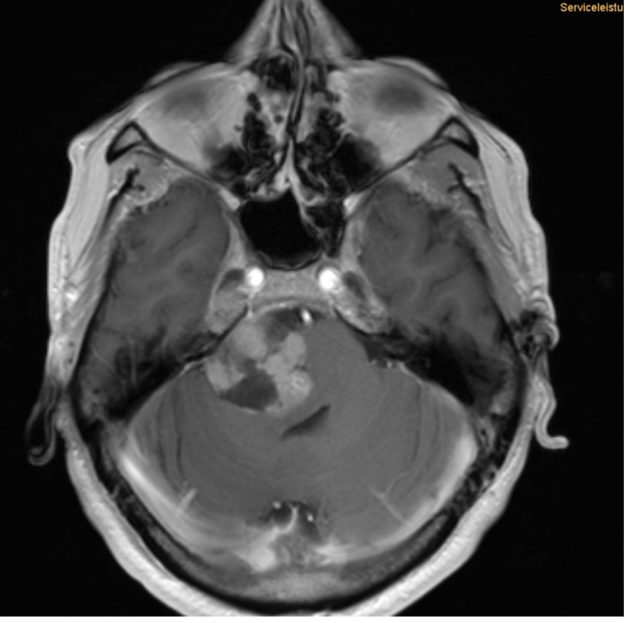

Μηνιγγίωμα περιοχής Επίφυσης

Ασθενής γυναίκα, 52 ετών η οποία παρουσίασε υπακουσία και επεισόδια πάρεσης του προσώπου. Ο απεικονιστικός έλεγχος με μαγνητική τομογραφία ανέδειξε ευμεγέθη όγκο στην περιοχή της επίφυσης (κωνάριο) με πίεση επί του μεσολοβίου, του τετραδύμου πετάλου και λοιπών εν’ τω βάθει δομών. Διενεργήθη δεξιά ινιακή, διασκηνιδιακή, διαδρεπανική προσπέλαση και ολική αφαίρεση της βλάβης. Η μετεγχειρητική αξονική…